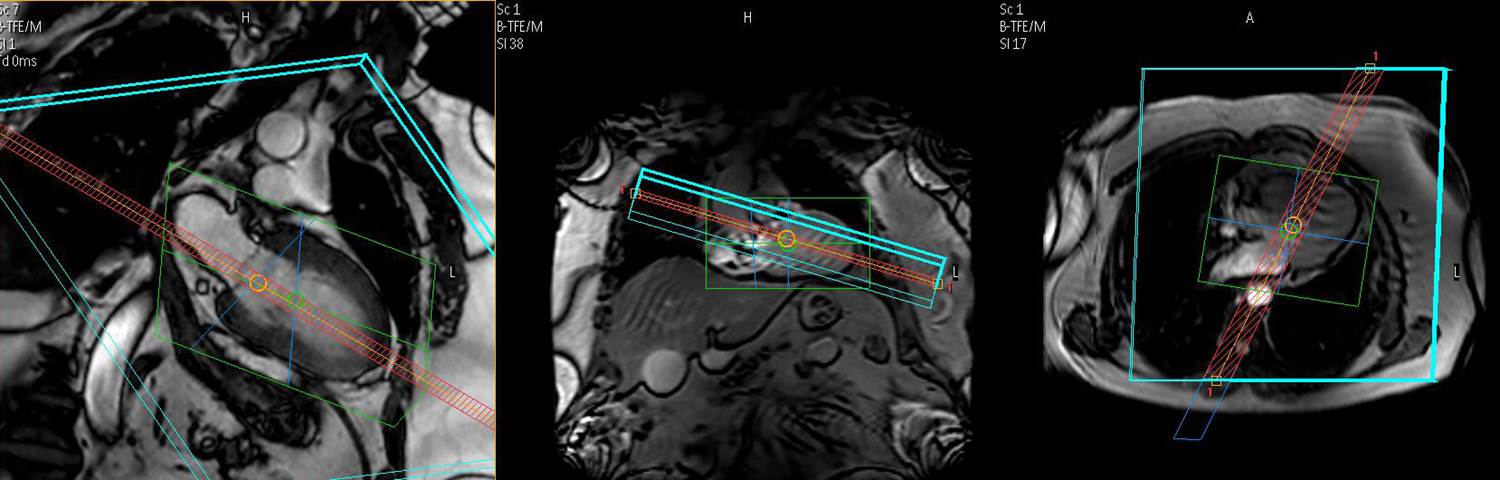

This workshop offers dedicated, state-of-the-art training in CMR stress testing and ischemic heart disease. Practical aspects are at the core of both lectures and hands-on training sessions which include live clinical cases at the scanner and extensive case reviews on dedicated workstations.